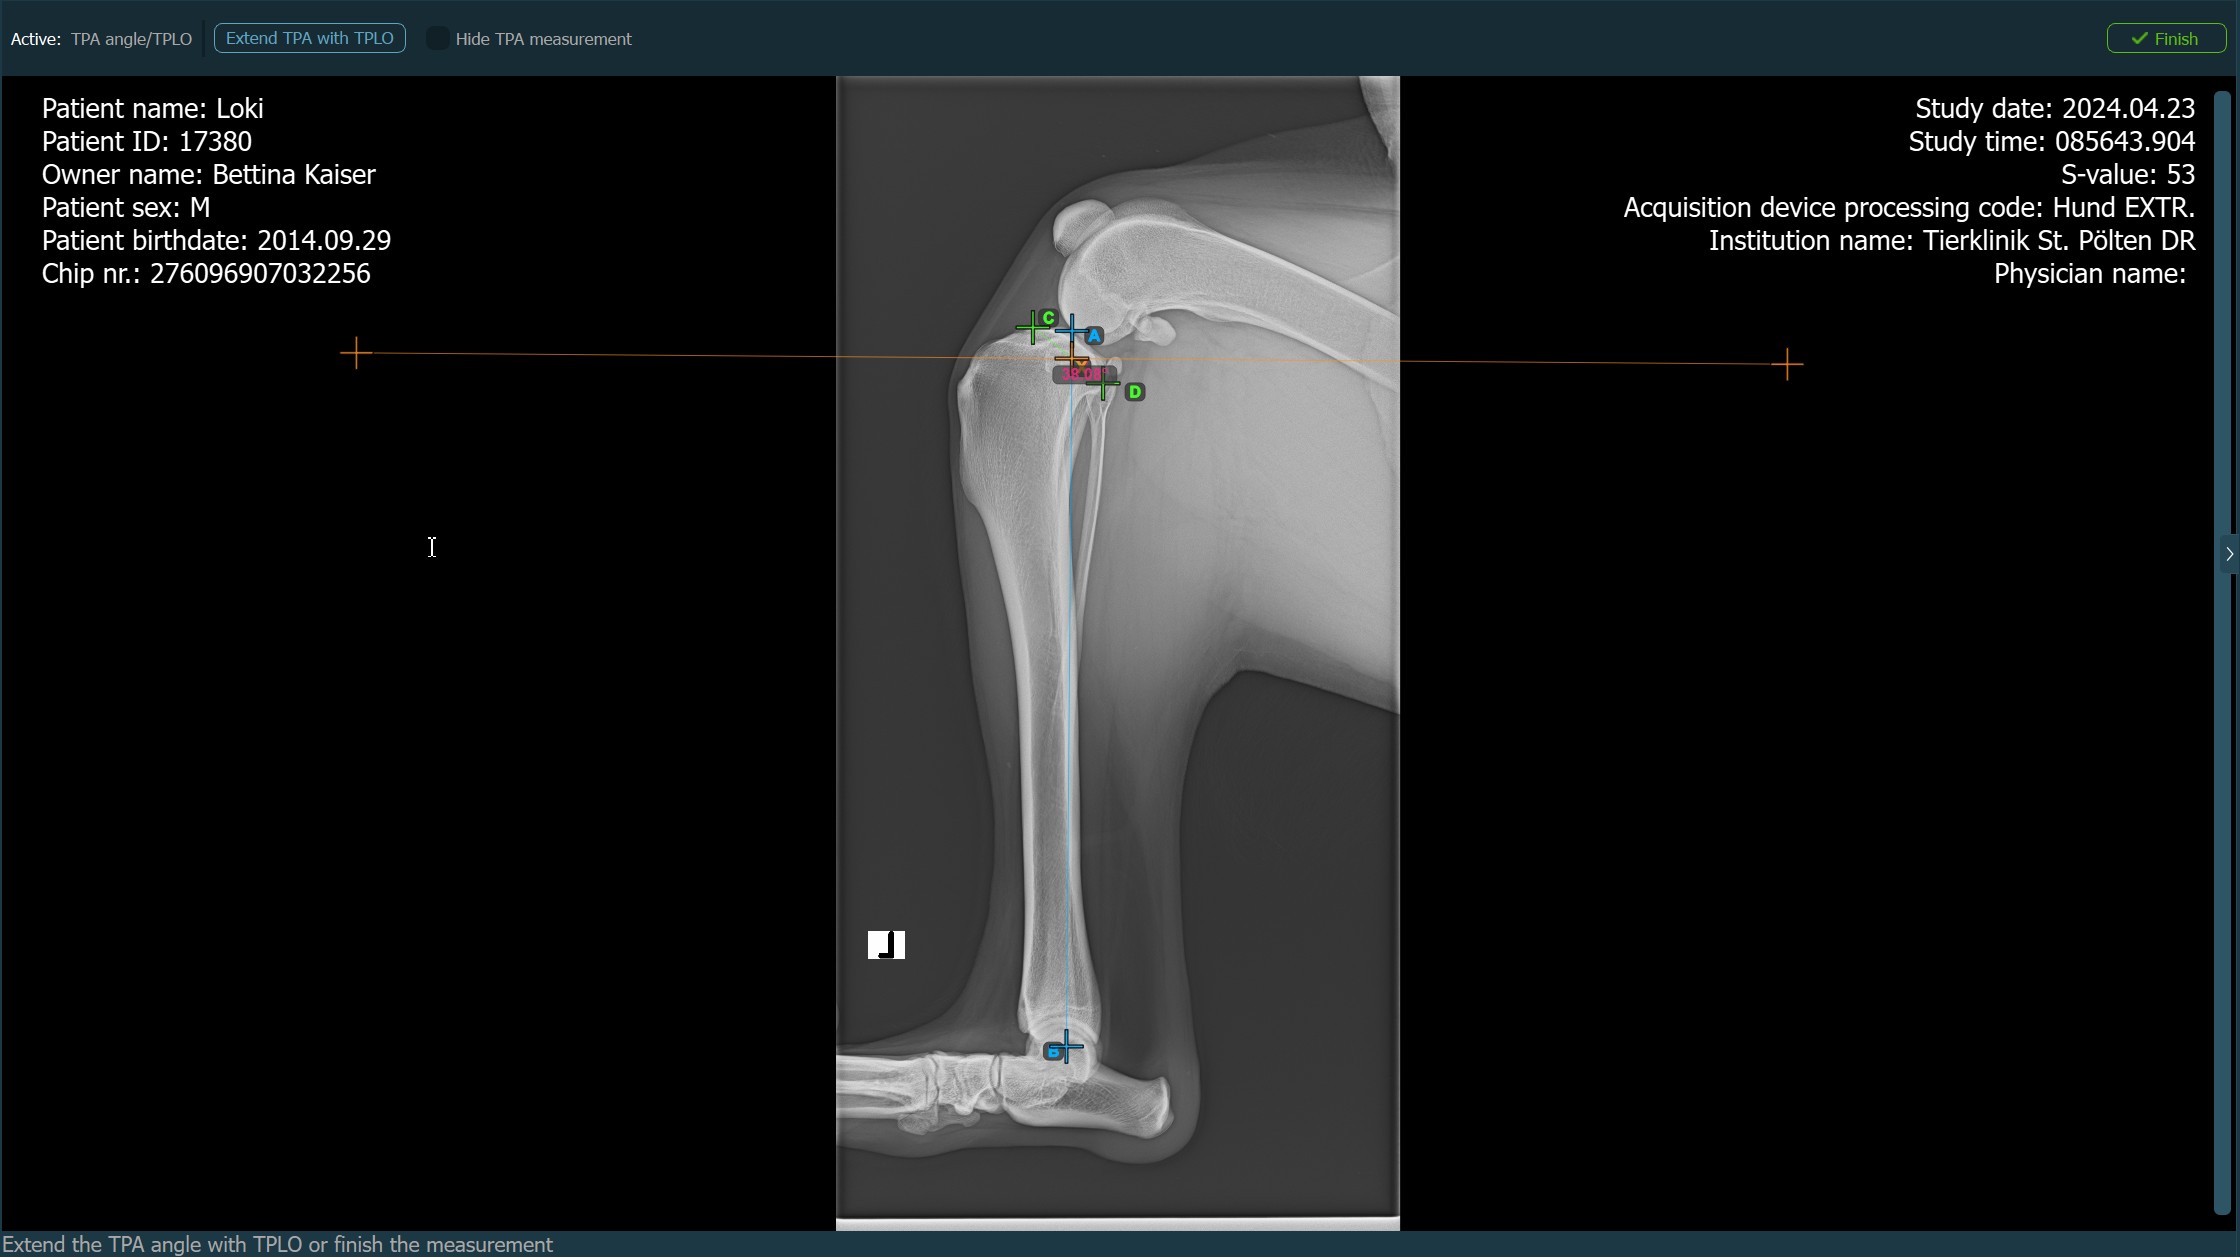

When the TPLO extension to the TPA Angle measurement is enabled, choose one of the available options from the advanced measurement mode toolbar to continue/complete the measurement. The TPA Angle measurement is automatically completed otherwise.

Press

Finishto confirm and complete the TPA Angle measurement without the TPLO extension.Activate the TPLO extension by using the

Extend TPA with TPLObutton.Hide/Show the TPA Angle measurement during the TPLO extension by toggling the

Hide TPA measurementcheckbox.![]()

Start the TPLO extension by marking the tibial crest. The sawblade size for the TPLO extension is automatically calculated as the distance between the Eminentia Intercondylaris and the point located two thirds along the line connecting the most caudal point of the tibial head and the tibial crest.

The image below depicts the usual placement of the tibial crest point on the tibial head.

Before completing the TPLO extension, users can modify the parameters of the measurement required to calculate the rotation distance for the procedure in the advanced measurement mode toolbar.

Press Calculate rotation distance to perform the required calculations for the TPLO procedure. The calculated rotation distance will be shown in the advanced measurement mode toolbar.

The TPA Angle measurement with the TPLO extension will be active until the user presses the Finish button in the right corner of the advanced measurement mode toolbar.